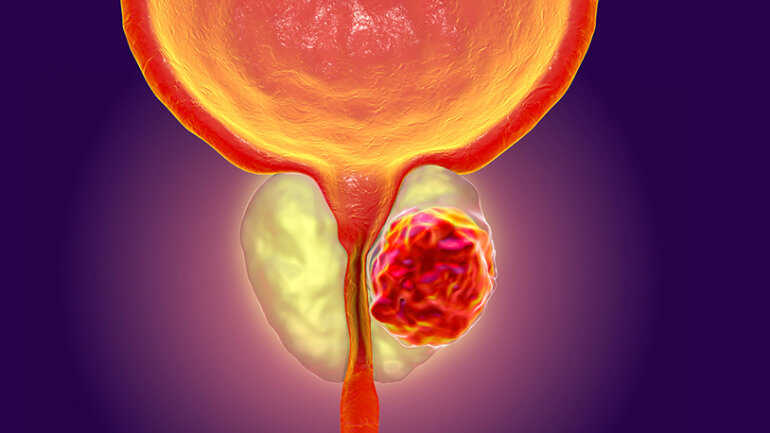

Στην αγαπημένη μέθοδο των ανδρών για την αντιμετώπιση της καλοήθους υπερπλασίας του προστάτη έχει εξελιχθεί το REZUM στην Ελλάδα , κατόπιν εισαγωγής της για πρώτη φορά προ τριετίας από την ομάδα του ιατρού Παναγιώτη Βεβελογιάννη Διευθυντού στην Κλινική Ελάχιστα Επεμβατικής Χειρουργικής Λιθίασης και Προστάτη στο Νοσοκομείο Μητέρα.

Έχοντας ξεκινήσει το 2015 στις Ηνωμένες Πολιτείες με την έγκριση του FDA και της Αμερικανικής Ουρολογικής Εταιρείας, το Rezum με τα εξαιρετικά αποτελέσματα που έχει επιδείξει, αποτελεί πλέον μετά από διεθνείς κατευθυντήριες γραμμές τον χρυσό κανόνα των ελάχιστα παρεμβατικών μεθόδων για την θεραπεία της καλοήθους υπερπλασίας ανδρών οι οποίοι θέλουν να διατηρήσουν τις ζωτικές λειτουργίες της στύσης και της εκσπερμάτισής τους.

Η επαναστατικότητα της νέας τεχνολογίας έγκειται στην διαχείριση των θερμοδυναμικών ιδιοτήτων του απλού ύδατος με έναν θεμελιωδώς διαφορετικό τρόπο από αυτόν που χρησιμοποιούσαμε για να μεταδώσουμε την ενέργεια μέχρι σήμερα , άλλον δηλαδή από την μέθοδο της αγωγής που προυπέθετε μεγάλα ποσά ενεργείας και απ’ευθείας επαφή με τον προστάτη , ώστε να αποφεύγεται η καταστροφή του οργάνου με όλες τις συνεπαγόμενες επιπλοκές που αυτό προκαλούσε.

Η ολιγόλεπτος έγχυσις ατμού συντελείται πλέον με την μέθοδο της συναγωγής, όπου έχουμε στοχευμένα μια ήπια διάχυση του αερίου μόνον στην κεντρική ζώνη του προστάτη , που προκαλεί και την σύνθλιψη της ουρήθρας , επιφέροντας μια ήπια και σταδιακή συρρίκνωση του βλαβερού τμήματος του αδένα και απελευθερώνοντας τον ασθενή από τα συμπτώματα σε διάρκεια δύο με τριών εβδομάδων.

Αποφεύγονται κατ ’αυτόν τον τρόπο η γενική νάρκωση, η νοσηλεία, οι αιμορραγίες, η ακράτεια και η απώλεια των ζωτικών λειτουργιών του ανδρός. Αντιθέτως μετά από μία ώρα ο ασθενής επιστρέφει στις καθημερινές του δραστηριότητες και μέσα στο επόμενο χρονικό διάστημα ανεπαίσθητα η ίδια η φυσική ίασις του οργανισμού αφομοιώνει και απορροφά τον θεραπευθέντα ιστό.

Αδιαμφισβήτητα πλέον και στην χώρα μας ο νέος χρυσός κανόνας για την αντιμετώπιση μικρότερων σχετικά αδένων προστάτη είναι το Rezum, καθώς για τους μεγαλυτέρους σε όγκο εξ’ αυτών είναι η Laser εκπυρήνιση του αδένα HoLEP, η οποία αποτελεί διεθνώς και την κορωνίδα των επεμβάσεων για τον προστάτη έχοντας εισαχθεί επίσης από εμάς προ τριετίας στην Αθήνα και διενεργείται επι της μεγαλυτέρας σειράς ασθενών Πανελληνίως ως επέμβασις εκλογής στο Τμήμα μας, έχοντας εκθρονίσει για πάντα την παλιά και καλή Turis , ως μια ελάχιστα επεμβατική τεχνική που αποτελεί μια πραγματική ευεργεσία για τον ασθενή.